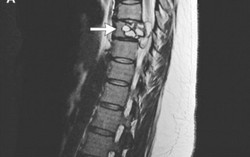

Đi khám tê chân, phát hiện sán dây cuộn trong cột sống

Phòng & chữa bệnh 15:21 13/07/2018Sau 3 tháng vật lộn với cảm giác tê chân và không thể đi đứng bình thường, một người phụ nữ 35 tuổi người Pháp bất ngờ phát hiện sán dây cuộn trong cột sống.